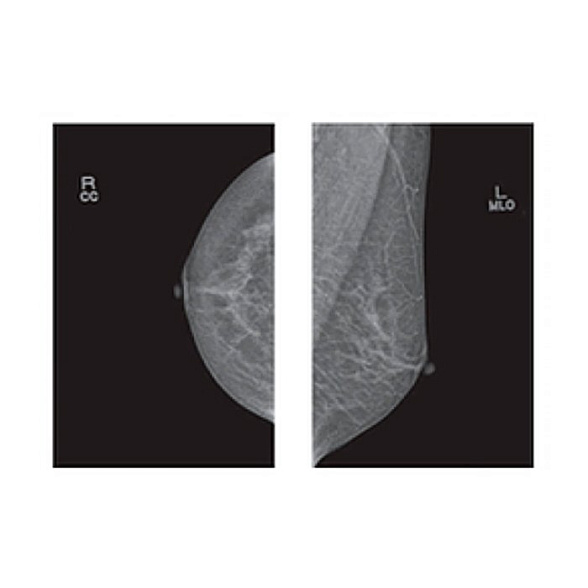

Ключевое преимущество PINKVIEW-AT — это оптимальное соотношение цены, качества и функциональности. Аппарат позволяет выполнять все необходимые стандартные проекции (краниокаудальную и медиолатеральную косую) с высоким качеством изображения на пленке, обеспечивая врачу-рентгенологу всю нужную информацию для постановки предварительного диагноза.

- Высокое качество визуализации: Оптимизированная рентгеновская трубка и система компрессии обеспечивают необходимую контрастность и детализацию снимков на маммографической пленке.

| Фотокассета (размер) | 18x24 см и 24x30 см |